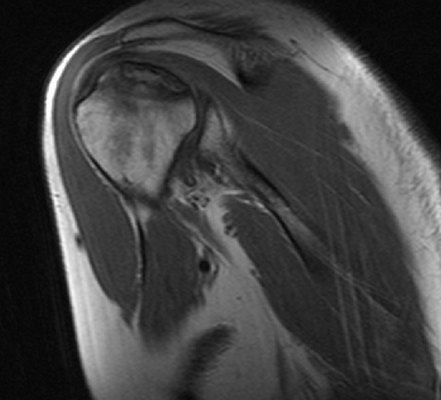

На серии МР-томограмм, взвешенных по Т1 и Т2, а также протонной плотности с использованием режима жироподавления в аксиальной, косой корональной и косой сагиттальной плоскостях определяются структуры правого плечевого сустава. Соотношение в суставе на момент исследования не нарушено. Субакромиальное пространство составляет 6 мм (сужено). Суставная впадина лопатки уплощена, контуры ее ровные, с признаками субкортикального остеосклероза. По краям суставной впадины лопатки имеются небольшие остеофиты. Головка плечевой кости округлой формы не деформирована. Суставной хрящ неоднородной структуры, неравномерно истончен, целостность его не нарушена.

Суставная губа на всем протяжении прослеживается, дегенеративно изменена, без отчетливых признаков нарушения целостности. Средняя суставно-плечевая связка неравномерно утолщена, без нарушения целости, но вокруг отмечается небольшое количество выпота. Сухожилие надостной мышцы на протяжении 24 мм (преимущественно в области мышечного брюшка) утолщено, разволокнено с признаками отека и участками обызвествления, преимущественно изменения отмечаются в передней порции волокон - повреждение сухожилия дегенеративного генеза. Вокруг мышечного брюшка надостной мышцы отмечается небольшой отек межмышечной клетчатки.

Сухожилие подлопаточной мышцы в области прикрепления к малому бугорку плечевой кости утолщено, минимально разволокнено, общая целость его и натяжение сохранены (изменения по типу тендиноза). Сухожилия подостной мышцы в области прикрепления к плечевой кости имеют неоднородную МР- структуру, за счет дегенеративных изменений, целость не нарушена. Сухожилия малой круглой мышцы не изменено. Визуализируется умеренное скопление свободной жидкости в полости плечевого сустава, умеренное в подклювовидной сумке. Сухожилия длинной головки двуглавой мышцы плеча не изменено, вдоль него минимальное количество выпота. Правый акромиально-ключичный сустав дегенеративно изменен: суставные поверхности имеют неровные контуры с наличием краевых костных разрастаний, сами суставные концы с субкортикальным остеосклерозом. Капсула сустава умеренно утолщена.

ЗАКЛЮЧЕНИЕ: МР-картина остеоартроза правого плечевого и акромиально-ключичного сустава I-II ст., признаков импинджмент синдрома с частичным повреждением сухожилия надостной мышцы, умеренно выраженные дегенеративные изменения сухожилия подлопаточной мышцы по типу тендиноза. Синовит. Умеренный теносиновит.